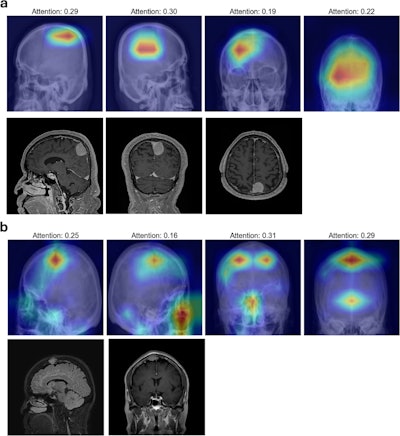

Grad-CAM Visualizations for clinoid and tuberculum sellae meningiomas from the internal dataset. (a): Grad-CAM heatmaps for clinoid meningioma display dispersed activations, with reduced localization to the clinoid region, indicating limitations in explainability despite accurate model predictions. (b): For tuberculum sellae meningioma, activation maps show scattered and weakly localized activations, highlighting challenges in visual explainability for deeper anatomical regions.Scientific Reports

Finally, Grad-CAM visualizations revealed that the model predominantly focused on specific regions of the cranial vault, particularly the frontal and parietal bones in cases of convexity and parasagittal meningiomas, which corresponded well with MRI findings.